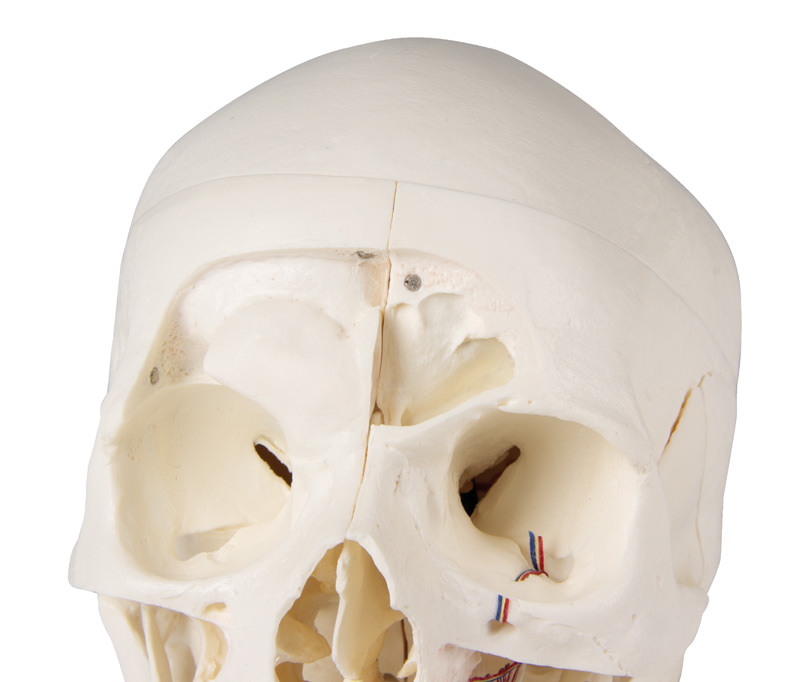

Das Schädeldach ist eröffnet und abnehmbar lässt aber die Schläfenbeine und ihre Nähte unberührt. Knöcherne Impressionen des sinus sagittalis, des sinus transversus und des sinus sigmoideus wie auch der Hirnhautgefäße sind bemalt. Die Schädelbasis ist sagittal geschnitten in der Form, dass der Schnitt auf einer Seite durch eine Siebplatte und ein weiterer Schnitt mit gleicher Ebene durch die andere Siebplatte des Siebbeins verläuft, was die Christa galli und die Lamina perpendicularis wie auch die ganze Nasenscheidewand intakt lässt. Die Strukturen der vorderen, mittleren und hinteren Schädelgrube sind einfach zugänglich. Man kann direkt die Nasenhöhle, die Nasenmuschel, das Septum sowie den knöchernen Rachenraum und Nasenrachenraum sehen. Die Nasenscheidewand kann aus den umgebenden Knochenstrukturen entnommen werden. Die Stirnhöhlen sind auf der einen Seite als Ganzes präpariert, auf der anderen Seite eröffnet, so dass sie voll zugänglich ist. Die Beziehung dieses Sinus zur Nasenhöhle ist klar zu erkennen, dies ist besonders wertvoll für HNO-Ärzte.

Auf einer Seite des Schädels wurde das Schläfenbein in situ belassen. Das andere Schläfenbein ist aus dem Schädel herausnehmbar. Ein Teil des Warzenfortsatzes und der Schläfenbeinschuppe zusammen mit dem Antrum mastoideum können herausgenommen werden und bieten freie Sicht auf das Innenohr. Alle drei Bogengänge sind sichtbar zusammen mit dem Verlauf des N. facialis, welcher nach hinten und dann nach unten verläuft und letztendlich durch das Foramen stylomastoideum hindurchtritt. Das herausnehmbare Schläfenbein zeigt einen vollständigen äußeren Gehörgang. Ein fast senkrechter Schnitt durch den Warzenfortsatz und dann weiter einwärts entlang der Fissura petrosquamosa teilt das Schläfenbein und die Position des Trommelfells ist zu sehen. Der Canalis caroticus ist wie auch die Cochlea eröffnet und zeigt den inneren Gehörgang und der Verlauf des Gesichtsnervs ist zu erkennen. Das ovale Fenster, die Bogengänge sowie Öffnung der Paukenhöhle sind zu erkennen.

Der Oberkiefer und der Unterkiefer zeigen die Strukturen des Gebisses, die Wurzeln, den knöchernen Rand des Alveolarfortsatzes sowie dentale Nerven und Gefäße. Die Oberkieferhöhle kann durch das Entfernen einer Klappe eröffnet werden. Die Zähne der rechten Unterkieferklappe sind halbiert und zeigen die inneren Strukturen der Zähne.